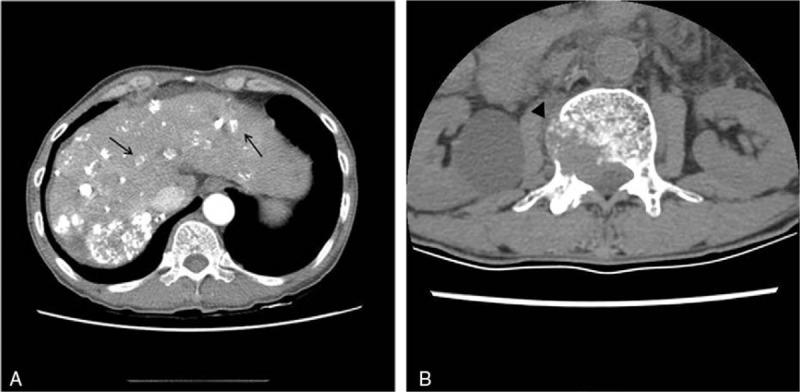

Chest computed tomography showed a large hematoma within the right pectoral muscle of the right upper chest and an exophytic metastatic mass in the right scapula with bony destruction, which caused the intramuscular hematoma. The final diagnosis was scapular metastasis of HCC presenting as acute bleeding and hematoma.

Selective right subclavian angiography showed a hypervascular metastatic lesion in the right scapula. Subsequently, embolization of the tumoral feeding artery using a microcoil was performed and tumoral bleeding was stopped.